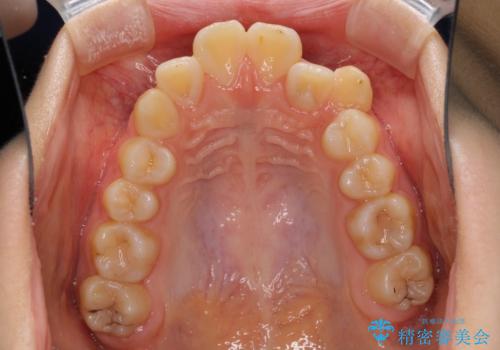

奥歯の咬み合わせは左右とも理想的なものでしたが、下顎前歯が1本欠損しているため、上下のバランスを保つことが難しい歯列でした。

唇を閉じたときに上顎前歯が下顎の唇に乗っかる印象があったため、八重歯の後方にある小臼歯を1本抜歯することとしました。

変則的な抜歯となるため、臼歯の咬合が理想的でなくなることが懸念されますが、インビザラインにて矯正治療を行うこととしました。